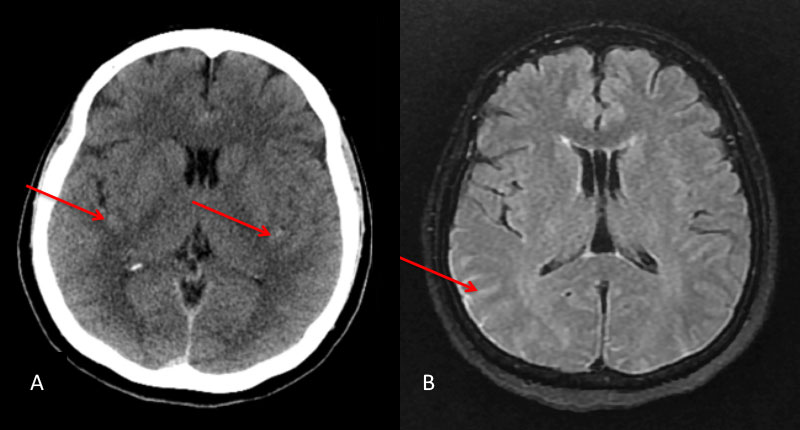

Figure 1: A) Non Contrast CT and B) MRI FLAIR studies demonstrate subtle Subarachnoid hemorrhage in the sylvian and parietal sulci (arrows)

A man in his 60’s presented with acute onset of abdominal pain radiating to the back. The initial evaluation focused on GI abnormalities which were unremarkable. A screening CT scan of the brain was performed and suggested a possible subarachnoid hemorrhage which was subsequently confirmed on MRI and lumbar puncture (Figure 1A and 1B).